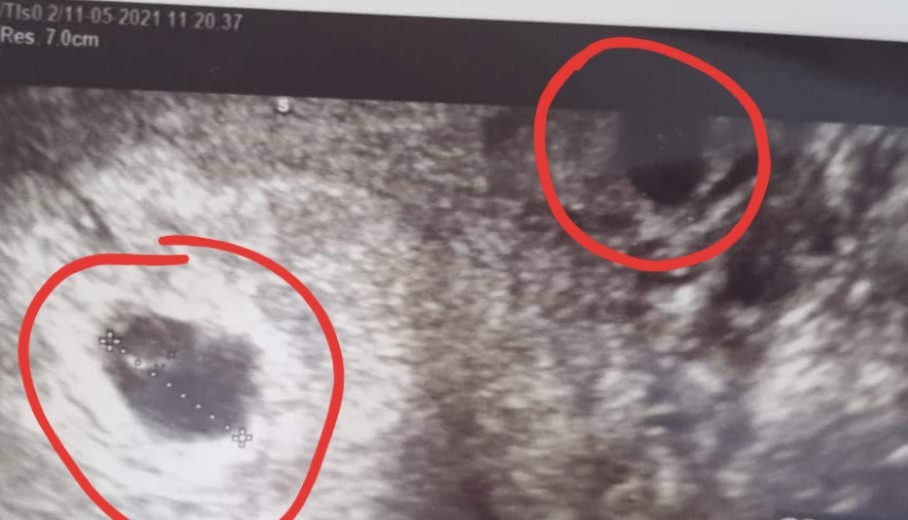

Cześć dziewczyny moj termin pokazuje na 04.01.2022 :) Ale mam pytaniedo Was czy Wy tu widzicie jeden czy dwa pęcherzyki ? pierwsze usg z 5 tygodnia ciazy drugie z 6 tygodnia ciazy. :D Bo już zguplam nic nie wspominal ginekolog o dwóch al3 za to przepisał i duphastpn i luteine A przy pierwszej ciazy pojedynczej tylko luteine.

Na tym drugim foto to jest pokazany, tak myśle ten „sprzęt” (wybacz mam mgle zapomniałam jak to się nazywa) który wkłada do pochwy

Niestety nie jestem specjalistą od usg, wiec raczej nie pomogę. Moim zdaniem każdy lekarz by zwrócił uwagę na dwa pecherzyki. Może to jajnik? Dziwne, ze na obu zdjęciach masz mierzony tylko jeden pecherzyk.